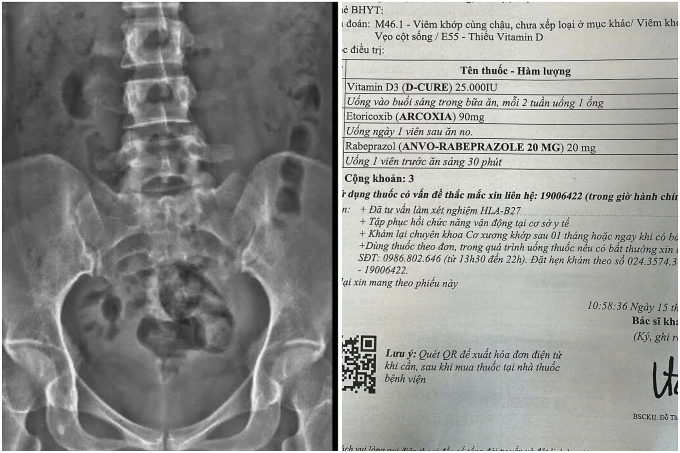

Kết quả chụp phim và một đơn thuốc của Linh sau thăm khám. Ảnh: Nhân vật cung cấp

Đến khi đi ngoài ra máu, cô mới đi kiểm tra. Kết quả cho thấy viêm loét dạ dày, HP, viêm khớp vùng chậu, vẹo cột sống, thiếu vitamin D. Bác sĩ phát hiện cô bị tăng huyết áp vô căn, cần theo dõi định kỳ. Nghe vậy, Linh thở dài. “Hóa ra, mất tiền còn kiếm lại được, mất sức khỏe là mất tất”.